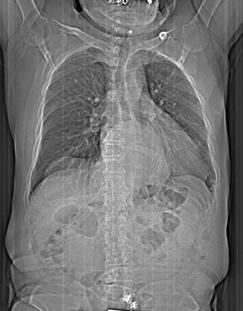

Figura 1. Fiziopatologia sindromului CRM. Țesutul adipos în exces sau disfuncțional, prin secreția de citokine și adipokine proinflamatorii, favorizează inflamația, stresul oxidativ, rezistența la insulină și disfuncția endotelială. Aceste procese duc la depunerea ectopică de grăsime (hepatică, epicardică, renală), hipertensiune și dislipidemie, cu progresie către boală cardiovasculară aterosclerotică și disfuncție cardiacă, precum și către BCR prin glomeruloscleroză și fibroză interstițială. Interacțiunile maladaptive dintre inimă și rinichi, la care se adaugă activarea neurohormonală și retenția hidrosalină, închid cercul vicios ce caracterizează sindromul cardio-reno-metabolic. Imagine preluată și tradusă de autori din documentul AHA5

Figura 2. Interrelația fiziopatologică cardio-renală în contextul sindromului metabolic. SRAA=sistemul renina-angiotensină-aldosteron